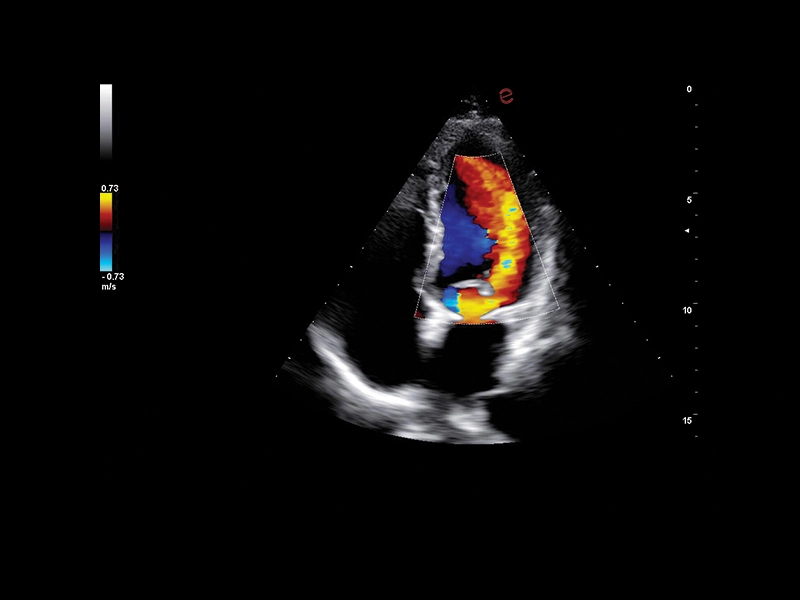

B-mode/M-Mode/CFM/Doppler/Power Doppler/microV

HD Color Doppler (CFM) i Power Doppler (PDI) kao i Directional Power Doppler (DPDI) sa visokom osetljivošću i definicijom.

XFlow, MicroV i MicroV HFR za povećanje osetljivosti i rezolucije u snimanju protoka krvi

BrightFlow – 3D kolor efekat

KLINIČKE SLIKE